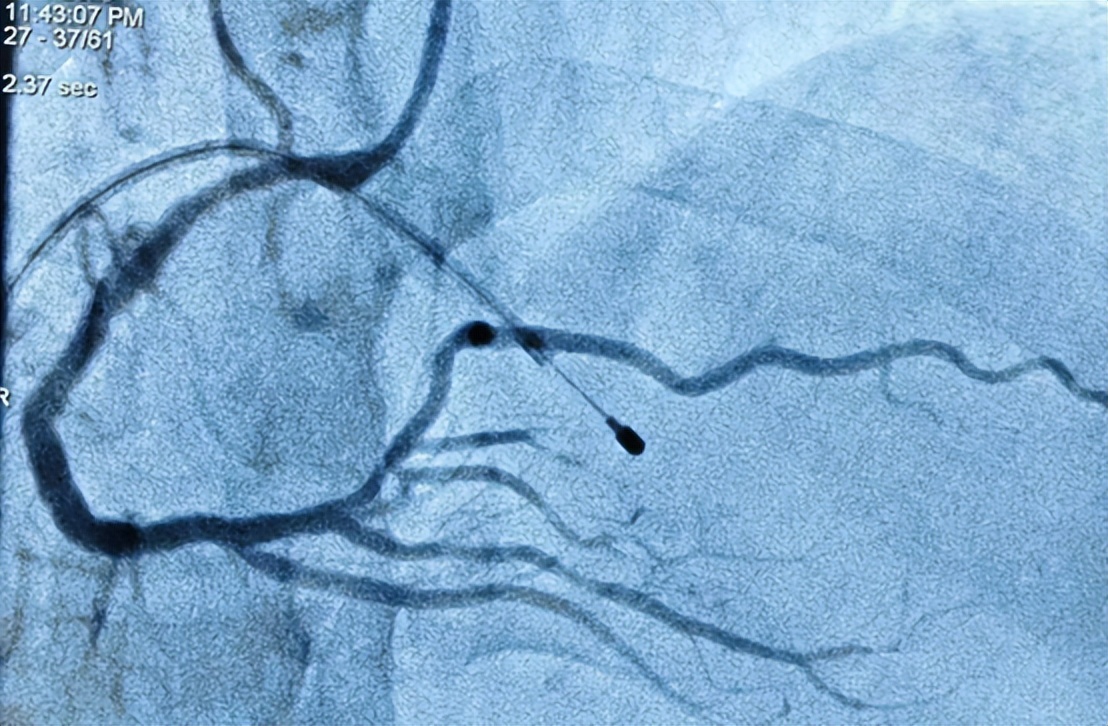

第2个是晚上急诊科收治的胸痛患者,经我科二线会诊后考虑急性下壁心肌梗死,立即启动急诊程序,患者心率偏慢,波动在40-50次/分,在快速完成造影后看到粗大右冠状动脉中远段闭塞,随即我们预判患者血流通过后,在再灌注的打击下,心率有可能进一步降低,甚至心脏停跳,所以果断的置入临时起搏器,在其保驾下行PCI术处理右冠状动脉闭塞病变。正如术前预测一样,导丝在经过闭塞病变后,跟着血流通过,患者血压逐渐下降,心跳完全依靠起搏,透视下见右心室搏幅明显减低,在静滴去甲肾上腺素后,患者血压逐渐回升,同时患者心率增快,出现室早二联律,立即予静推胺碘酮后,早搏逐渐减少至消失,心率稳定,后继续手术成功于闭塞段植入1枚支架,术后患者右冠状动脉完全恢复TIMI 3级血流,症状好转,无不适。

右冠状动脉中远段闭塞

术后(红箭头指示临时起搏器电极)

术后右冠状动脉远端